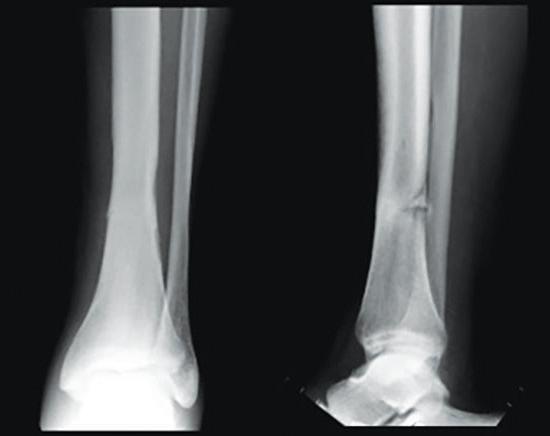

To my surprise, I not only had one, but three stress fractures on my tibia and ankle.

Stress fractures are tiny cracks in a bone. They’re caused by repetitive force, often from overuse — such as repeatedly jumping up and down or running long distances. Stress fractures can also develop from normal use of a bone that’s weakened by a condition such as osteoporosis.

Stress fractures are most common in the weight-bearing bones of the lower leg and foot. Track and field athletes and military recruits who carry heavy packs over long distances are at highest risk, but anyone can sustain a stress fracture. If you start a new exercise program, for example, you might develop stress fractures if you do too much too soon.